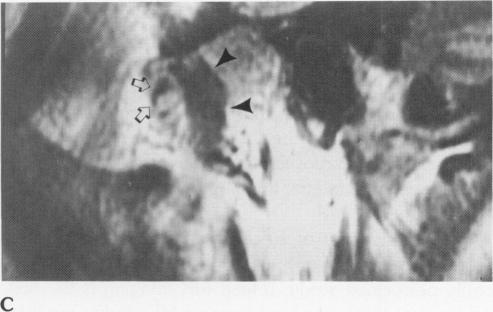

Temporomandibular joint imaging.

Anesth Prog. 1990 Mar-Jun;37(2-3):121-6.